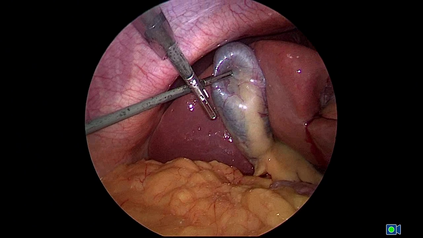

Large Vision-Language Models offer a new paradigm for AI-driven image understanding, enabling models to perform tasks without task-specific training. This flexibility holds particular promise across medicine, where expert-annotated data is scarce. Yet, VLMs' practical utility in intervention-focused domains--especially surgery, where decision-making is subjective and clinical scenarios are variable--remains uncertain. Here, we present a comprehensive analysis of 11 state-of-the-art VLMs across 17 key visual understanding tasks in surgical AI--from anatomy recognition to skill assessment--using 13 datasets spanning laparoscopic, robotic, and open procedures. In our experiments, VLMs demonstrate promising generalizability, at times outperforming supervised models when deployed outside their training setting. In-context learning, incorporating examples during testing, boosted performance up to three-fold, suggesting adaptability as a key strength. Still, tasks requiring spatial or temporal reasoning remained difficult. Beyond surgery, our findings offer insights into VLMs' potential for tackling complex and dynamic scenarios in clinical and broader real-world applications.